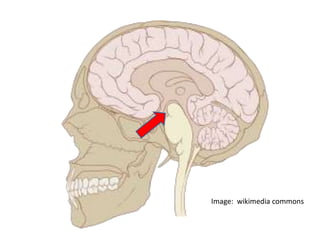

Image: wikimedia commons

Cortico-striatal loop